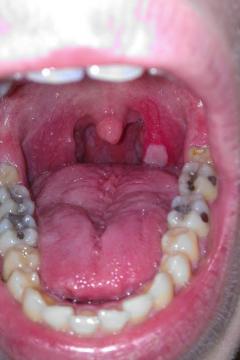

Biele fľaky v hrdle

Pro větší náhled klikněte na obrázek

Biele fľaky v hrdle Michal92 - 6.7.2014 14:09:53

Dobrý deň, prekonal som rozsiahlu infekciu hrdla, dosť ma bolela ľavá strana hrdla na ktorom sa mi vytvoril biely hnisavý fľak, a opuchli mi mandle na tejto strane Momentálne beriem antibiotik 10ty deň, mandľa odpuchla, aj bolesť hrdla sa stratila no ten fľak na hrdle stále mam. Antibiotika ešte na 5 dni mám, 2x denne kloktam šalviový čaj. Viete mi prosím poradiť čo by ešte prispelo k rýchlejšiemu vyliečeniu hrdla ? Ďakujem